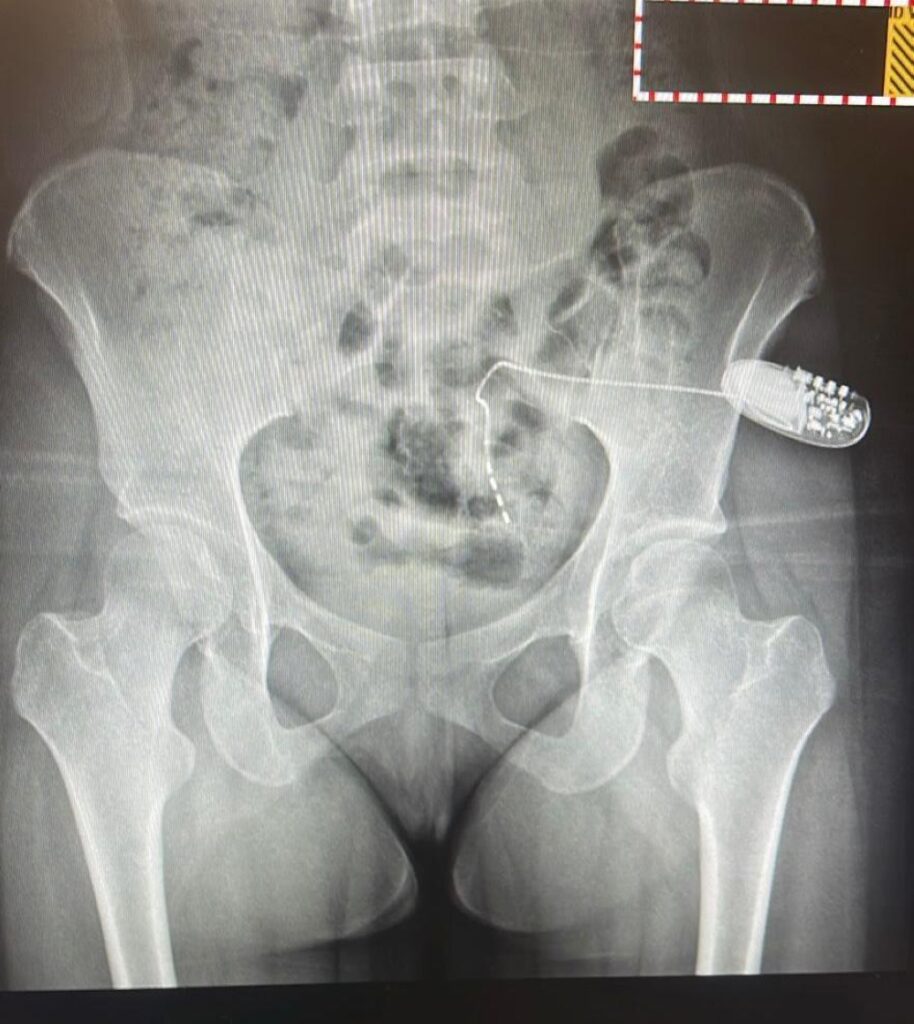

وأوضح الفريق الطبي بقيادة د خالد الخريصي استشاري جراحة اعصاب المثانة والجراحة الترميمية للمسالك البولية أنه بعد إجراء الفحوصات التشخيصية المتقدمة، ومن أبرزها فحص ديناميكية المثانة، تم تحديد السبب الرئيسي لاحتباس البول.

وتقرر إجراء عملية زراعة جهاز التحفيز العصبي العجزي، وهي من العمليات النوعية والمتقدمة في جراحات المسالك البولية وأعصاب المثانة.

وتكللت العملية ولله الحمد بالنجاح ، حيث استعادت المريضة قدرتها على التبول بشكل طبيعي وكامل وتمكنت من الاستغناء نهائياً عن القسطره البولية ما انعكس إيجاباً على حالتها الصحية وجودة حياتها.

وأكد الفريق الطبي أن تقنية التحفيز العصبي العجزي تُعد من الحلول العلاجية المتقدمة للمرضى الذين يعانون من اضطرابات التحكم في المثانة أو احتباس البول الناتج عن خلل في الإشارات العصبية بين المثانة والجهاز العصبي.